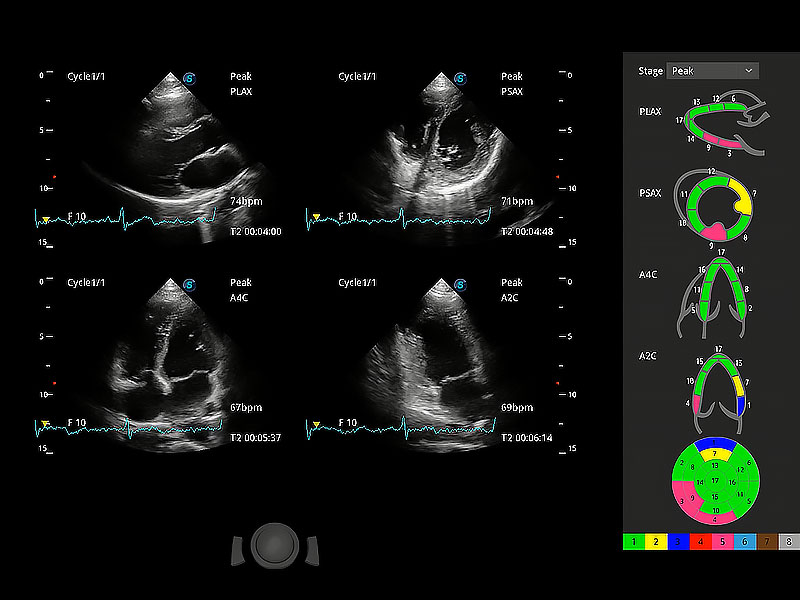

ProPet 80 配備了豐富的心臟探頭群、先進的成像技術(shù)和專業(yè)的心臟測量工具,可幫助動物醫(yī)生為不同體型和生理結(jié)構(gòu)的動物提供心臟和心肌功能的全面評估。

通過心肌識別技術(shù)與二維斑點追蹤技術(shù)相結(jié)合,對心臟的超聲圖像進行量化分析。計算心肌17個節(jié)段的應變、應變率、速度、位移等,并通過牛眼圖的形式進行呈現(xiàn)。

具備多種協(xié)議可選,同時支持17階段劃分法和專業(yè)的SE報告。